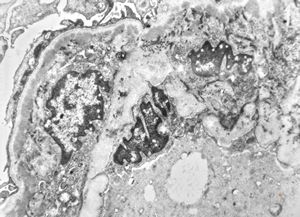

M,17y. | Alport syndrome - split and laminated basement membranes